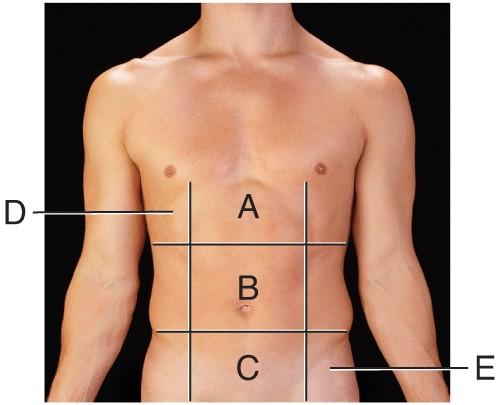

Name the region B.

middle hypochondriac

hypogastric

epigastric

Umbilical

Umbilical

Name the region A.

epigastric

umbilical

right hypochondriac

hypogastric

epigastric

Name the region E.

left hypochondriac

right lumbar

epigastric

left iliac

left iliac

Name the region C.

middle iliac

epigastric

umbilical

hypogastric

hypogastric

Name the region D.

Right Hypochondriac

Left Hypochondriac

epigastric

Right Lumbar

Right Hypochondriac

The liver is found in the region labeled:

A